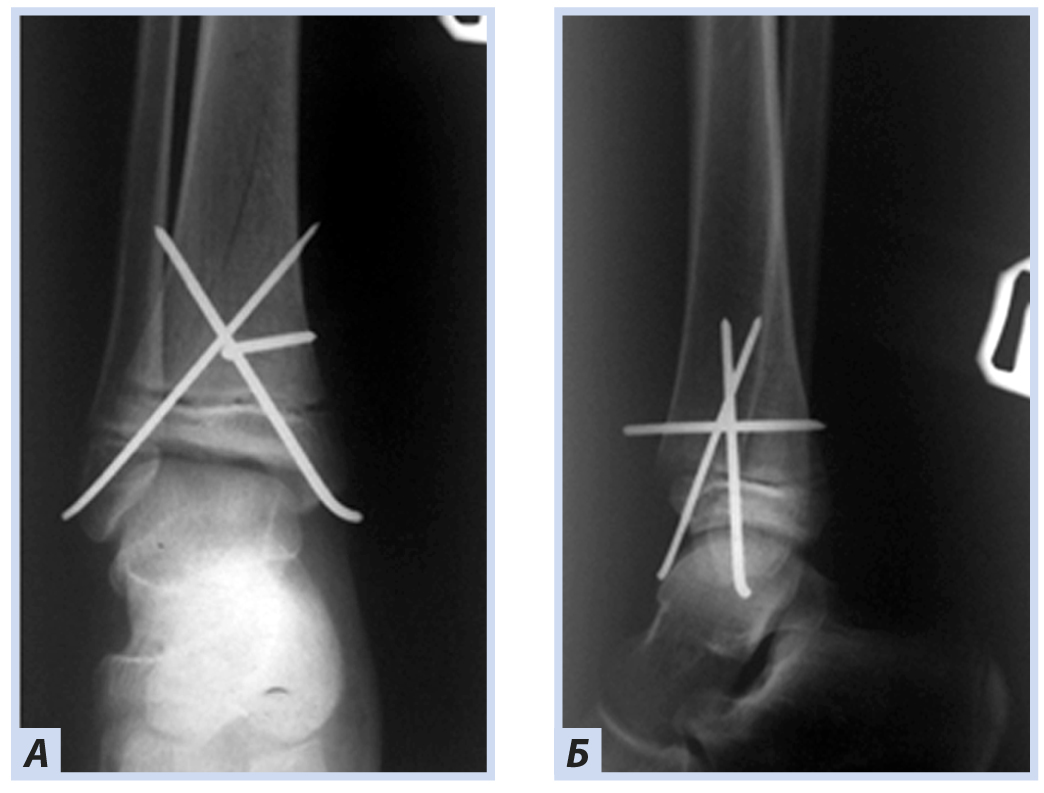

Клиническое наблюдение 1

Девочка, 10 лет, диагноз: «Закрытый дистальный остеоэпифизеолиз правой большеберцовой кости, Salter–Harris, II тип». Травму получила, упав с самоката, вследствие чрезмерного сгибания стопы кзади. По механизму травмы — ротационно-флексионный перелом дистального отдела костей голени. По данным компьютерной томографии выявлена значительная степень (5 мм) смещения отломков. Учитывая возраст больной, остеосинтез выполнен закрыто перекрещивающимися спицами. Дополнительная иммобилизация осуществлялась в задней гипсовой лонгете до коленного сустава. Контрольные рентгенограммы выполняли через 4 и 6 нед. после репозиции. Спицы удалены через 6 нед., конфигурация сустава восстановлена полностью (рис. 1–5).

Рис. 1. Девочка, 10 лет. Рентгенограммы дистального отдела костей правой голени. Дистальный остеоэпифизеолиз правой большеберцовой кости, Salter–Harris II тип: А — прямая проекция; Б — боковая проекция.

Рис. 3. Тот же пациент. Рентгенограммы дистального отдела костей правой голени. Полифокальный остеосинтез спицами: А — прямая проекция; Б — боковая проекция.